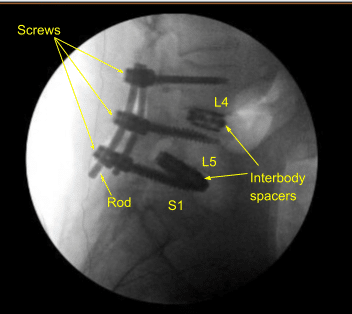

Interbody spaces were irrigated clear, packed with morselized autograft from the decompression as well as demineralized bone matrix allograft, and then an expandable titanium interbody spacer was placed under sterilely draped fluoroscopic guidance in AP and lateral views into proper position. Neuromonitoring signals were stable. Bilateral L3-4 neurolysis was performed with Metzenbaum-Penfield technique and confirmed with nerve hook circumferentially.

The wounds were irrigated clear. Precut-precontoured titanium rods were selected and placed across the tulips from L3 to L5 bilaterally and secured with locking caps which were all final tightened with a torque and anti torque device.

Bilateral transverse processes were decorticated with electric high-speed drill from L3 to L5 and morselized autograft and allograft mixed with bone marrow aspirate from a separate incision at the superior iliac crest was all combined for the posterolateral arthrodesis graft as well as bone morphogenic protein. No CSF leak or durotomy was appreciated after inspecting the thecal sac.